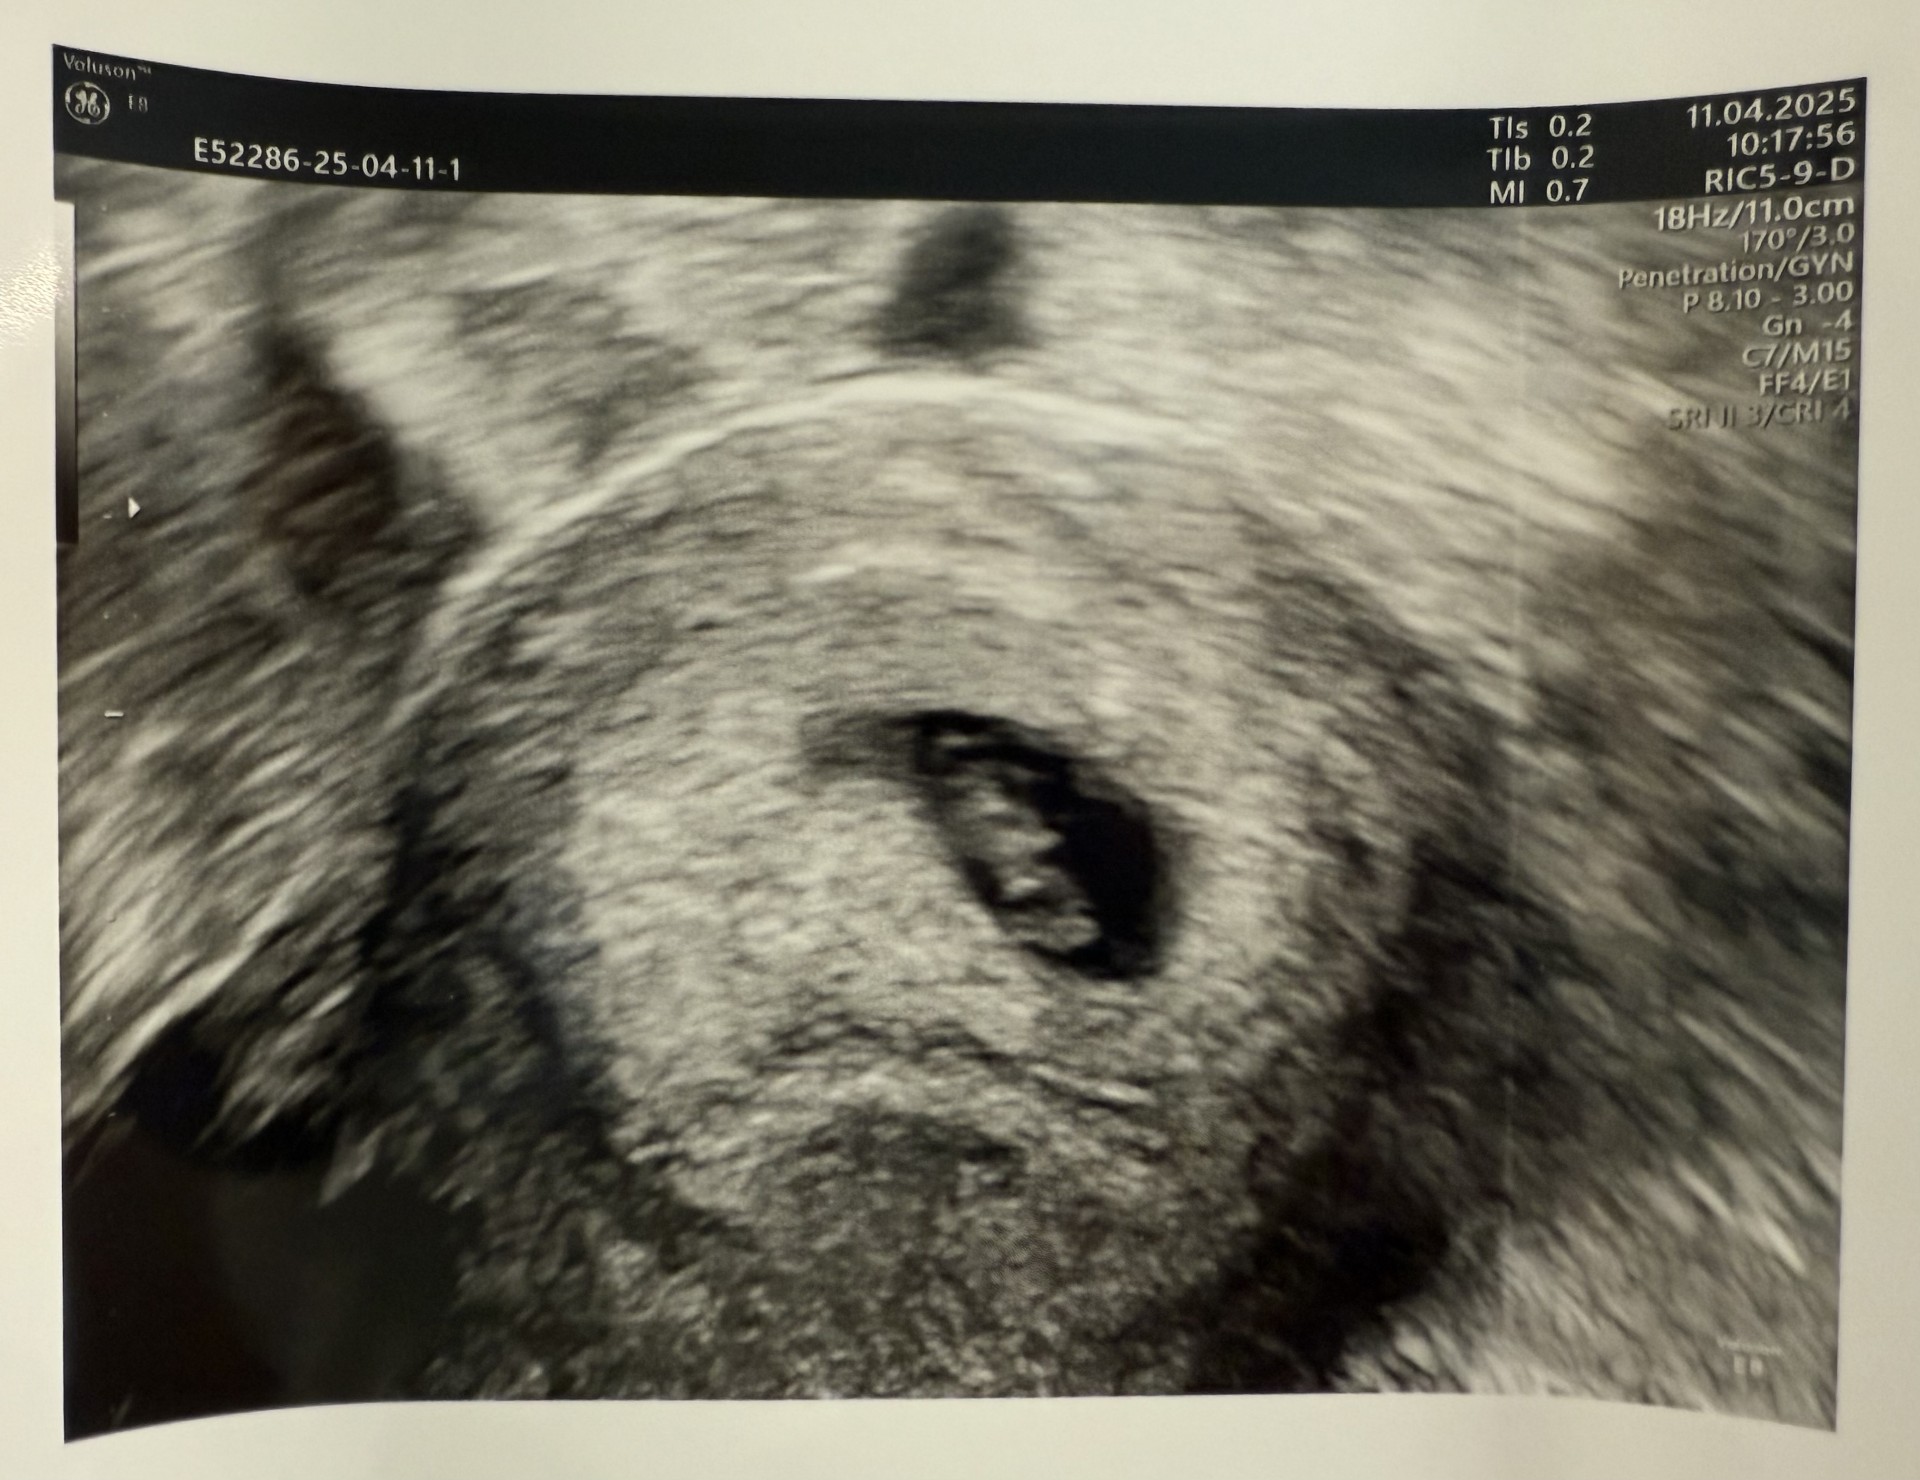

Selv om svangerskapet kan være litt tøft, må jeg være helt ærlig og si at det var helt magisk å komme til den første ultralyden i uke 7. Selv om jeg ikke så så mye annet enn en liten bønne, fikk jeg høre de helt perfekte hjerteslagene og se det lille hjertet bevege seg. Tenk at den lille, som bare er 1 cm, allerede kan ha et så sterkt hjerte.